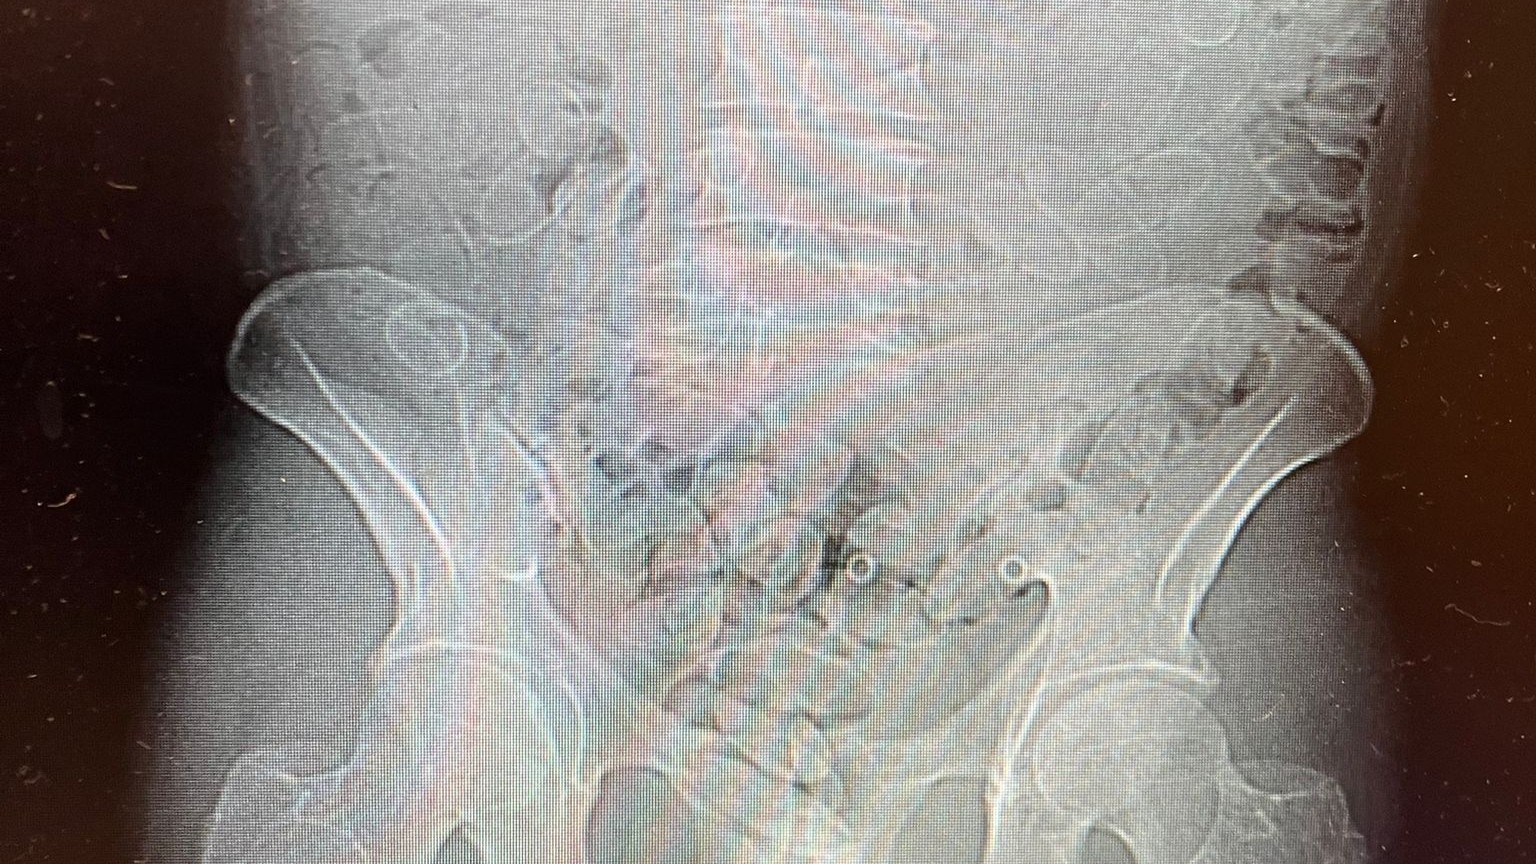

Mężczyzna, obywatel Polski, przyznał, że połknął 88 dodatkowych kapsułek z kokainą. Został przewieziony do szpitala, gdzie wykonane badanie tomografem komputerowym potwierdziło obecność narkotyków w organizmie.

Badania laboratoryjne przeprowadzone przez Pomorski Urząd Celno-Skarbowy w Gdyni wykazały, że łącznie zabezpieczono 89 kapsułek o wadze blisko 0,8 kilograma. Czarnorynkowa wartość narkotyków została oszacowana na prawie 300 tysięcy złotych. Decyzją sądu 40-latek został tymczasowo aresztowany na trzy miesiące.